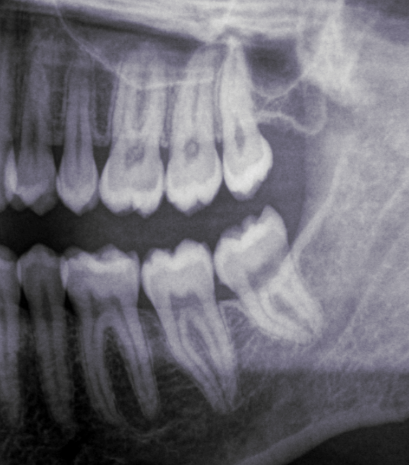

Look at these x-rays:

This patient was a female in her mid-30s. We will call her FA. As you can see, she only keeps her left wisdom teeth. At the age of 15, FA’s dentist wrongly diagnosed all her four wisdom teeth as impacted and recommended her to get them all out. FA was scheduled for two appointments: one to remove her right ones, and the other for the left ones.

Being 15 years old, I can imagine her wisdom teeth were still forming, deep in the bone. Maybe a big osteotomy (bone removal) was necessary to get to them. The issue of young teenagers (when not children) getting their wisdom teeth removed is also quite outrageous, but this article is long enough as it is already, so I won’t cover it here. The thing is that her post-operatory period was absolutely awful, so much so, that she refused to go get her remaining wisdom teeth removed.

Her case serves as a perfect illustration of three issues that I often denounce on this project: dentists failing to see that a wisdom tooth does have space to come in; dentists removing all four wisdom teeth automatically and without further reflection; and mutilations.

Her left wisdom teeth, also diagnosed as impacted back then, are obviously not impacted! Having examined her mouth, I can confirm they are perfect, ideally erupted and taking part in chewing like the normal teeth they are. Yet, they were diagnosed as impacted, with no place and problematic. This is nothing short of horrifying.

And I can very confidently say that her right molars were not impacted either, because of her wide retromolar spaces to the right (that is, the spaces behind her second molars), because we can be sure that her dentist was not able to properly diagnose impactions, and because of how ideally positioned and erupted her remaining wisdom teeth are. And no, she wasn’t having any kind of symptoms, discomfort or infections. Nor did she need the removal for any orthodontic or surgical reasons.

In a nutshell: she was mutilated.